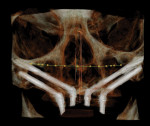

In cases where the residual maxillary bone is insufficient, especially in the paranasal region or lateral pyriform rim and when the sinus pneumatization is anterior to the canine region, and multiple grafting procedures are contraindicated, the use of zygomatic implants may be an option (Figure 3).2 This may allow for immediate stabilization of the dental implants and immediate function of a stable fixed prosthesis. Brånemark initially described using the zygomatic process to allow longer implants (30-mm to 55-mm length) to be placed and achieve a higher insertion torque.1 Multiple authors have published on the use of zygomatic implants for the immediate stabilization and loading of a full-arch fixed prosthesis in the severely resorbed maxilla.13-16

Variations of incorporating zygomatic implants into the severely resorbed maxilla may be part of a conventional type of All-on-4 treatment procedure when sufficient bone exists in the paranasal region for the placement of anterior implant fixtures (Figure 7 through Figure 10). When the paranasal region will not accommodate implant placement, this approach can be expanded to the quad zygoma procedure where two zygomatic implants are inserted in each upper quadrant bilaterally (Figure 11 through Figure 16).18,19